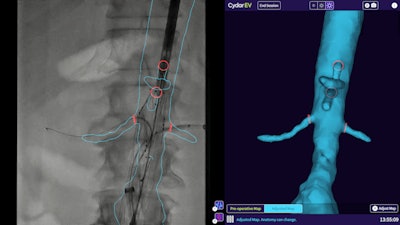

Cydar EV Maps software supports planning, real-time 3D image guidance, and postprocedure review of endovascular surgeries. Image courtesy of Philips Healthcare.

Cydar EV Maps software supports planning, real-time 3D image guidance, and postprocedure review of endovascular surgeries. Image courtesy of Philips Healthcare.Featuring cloud-based artificial intelligence (AI) and computer-vision technology, EV Maps facilitates creation of a patient-specific 3D map of the target vasculature that surgeons can use to plan surgery, Philips said. The software then utilizes these maps to augment intraoperative live image guidance, updating the maps in real-time to account for deformations, such as guidewires and instruments that deform the patient's blood vessels.

These capabilities yield approximately 50% lower radiation exposure, as well as less fluoroscopy time, and up to 20% faster procedure time, according to Philips. EV Maps has received U.S. Food and Drug Administration (FDA) 510(k) clearance, as well as the CE Mark.